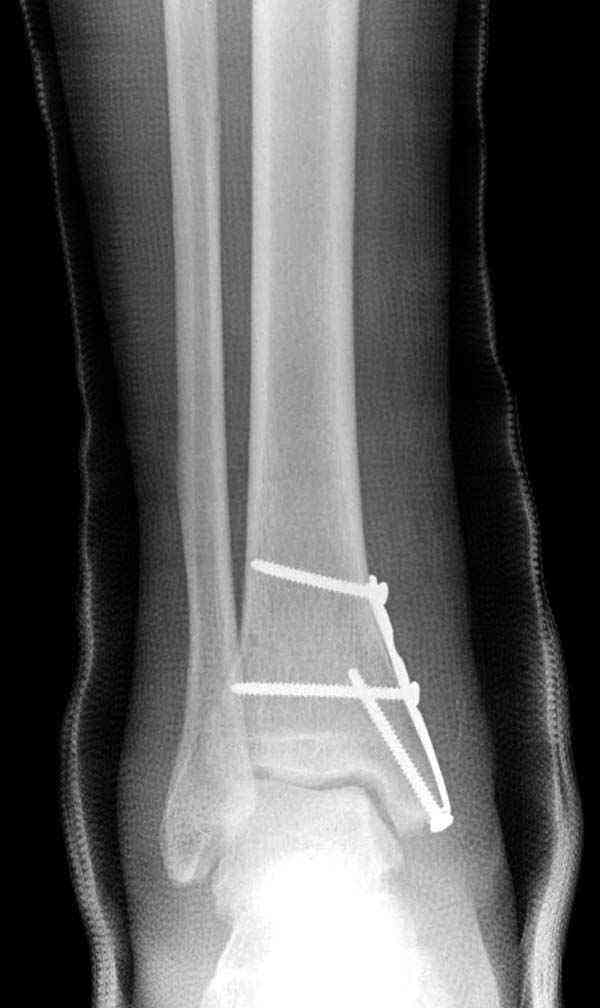

Случай прошлого года:пациентка-молодая ,крупная женщина ,30лет.Травма в начале апреля 2009г-пронационный перелом лодыжек с подвывихом стопы.Ко мне обратилась через 35 дней,прооперирована 22.05.2009г.Внутренняя лодыжка фиксирована по Веберу,наружная реконструктивной пластиной с наложением болта-стяжки.Иммобилизация "сапожок" в течении месяца,затем пригипсовано "стремя".Гипс снят 10.07.2009г

Достаточно быстрое восстановление функции.В октябре 2009г-почувствовала боль,в области рубца над гайкой открылся свищ.На Р-граммах-консолидация переломов и смещение гайки по стяжке.10.11.2009г-конструкции удалены,санация,заживление ран.В настоящее время пациентку ничего не беспокоит.На операции-раскручивание гайки-болталась на конце стяжки.Вопросы:какой механизм раскручивания и что я неправильно сделал?Свои версии:1)в области синдесмоза успела образоваться рубцовая ткань,которая при движении в суставе"пружинила",поскольку голеностопный сустав является спиральным, то и биомеханика подобна кривошипному механизму.2)Реконструктивная пластина не "реконструировалась" по форме лодыжки.Наложил,как есть.То есть подпружинивала сама пластина.Ну,это мои догадки.Что нужно,чтобы избегать впредь таких,пусть и не "страшных"осложнений:Рассверливать через лодыжку область синдесмоза?Ставить шайбу-гровер?Тщательно моделировать пластину?Прилагаю сравнительные снимки-сразу после операции и перед удалением конструкции.

Визуально никаких вопросов по репозиции не было.Да и на основании чего сомнения,что наружная лодыжка не полностью репонирована или прорезалась проволка ???Я не вижу...Снимок после репозиции справа.

Реконструкционные пластины на лодыжке очень грубые, и из-за тонкого слоя кожи над дистальным концом малоберцовой могут осложниться пролежнями кожи изнутри.

Нет первичных снимков, перелом очень низкий и под большим сомнением диагноз разрыва синдесмоза. Медиальная сторона отрепонирована на "хорошо" и, по-видимому, прорезание проволоки произошло во время операции. Без снимков трудно судить о высоте малоберцовой, а лодыжка находится в варусе. Лагирование получилось, но возле тонких шурупов передне-задний шуруп выглядит немного тяжеловато.

Во всех руководствах АО имеется описание техники применения низкопрофильных пластин 1/3 трубки, которые могут быть применены для фиксации наружной лодыжки. Фиксацию проводят кортикальными 3.5 мм шурупами, и если дистальная фиксация недостаточная, тогда усиливают конструкцию созданием hook plate. Сгибая конец пластины на последнем отверстии, внедряют его в дистальный отдел, и тем самым создается дополнительная фиксация.